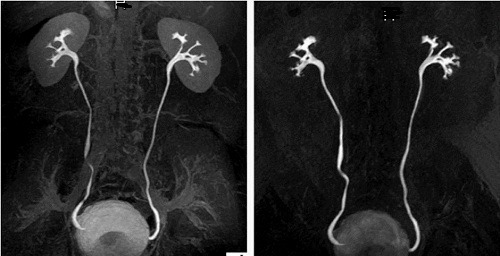

یک تجزیه و تحلیل گذشته‌نگر بر روی داده‌های بالینی ۱۶ بیمار زن که بین ژوئیه و سپتامبر ۲۰۲۴ تحت عمل جراحی داخل کلیوی رتروگراد (fURS) برای سنگ‌های دستگاه ادراری فوقانی در موقعیت شکم و لگن در بیمارستان ما قرار گرفتند، انجام شد. همه بیماران با استفاده از یورتروسکوپ‌های انعطاف‌پذیر تحت درمان قرار گرفتند و قبل و بعد از عمل، سی‌تی‌اسکن برای ارزیابی نتایج جراحی دریافت کردند.

همه جراحی‌ها با موفقیت در موقعیت شکم و لگن انجام شد و میانگین زمان عمل ۶۲.۲۵ ± ۲۵.۹۲ دقیقه بود. میزان دفع فوری سنگ ۱۰۰٪ بود و هیچ عارضه‌ای مشاهده نشد.

جراحی داخل کلیوی رتروگراد در موقعیت شکم و لگن، یک درمان مؤثر برای سنگ‌های دستگاه ادراری فوقانی در بیماران زن است. این موقعیت، دسترسی از طریق اورتروسکوپی به لگنچه کلیه و قرار دادن غلاف‌های راهنمای حالب را تسهیل می‌کند، میزان دفع فوری سنگ را بهبود می‌بخشد، فشار داخل کلیوی را کاهش می‌دهد و یک روش درمانی کارآمد، اقتصادی و ایمن را ارائه می‌دهد.